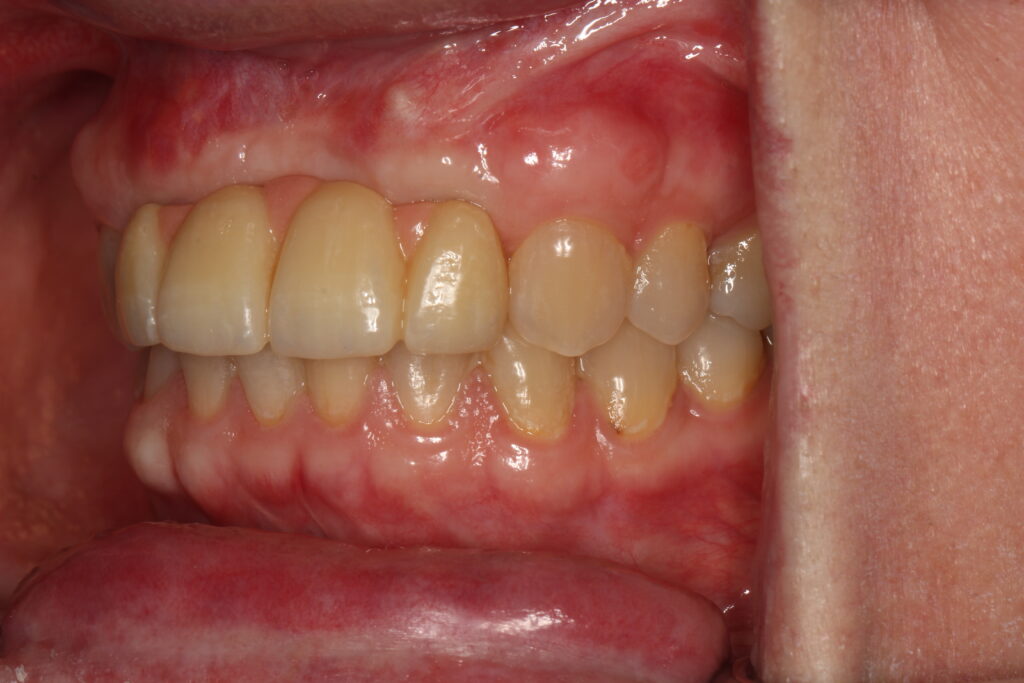

A selection of partial arch fixed implant bridge patients